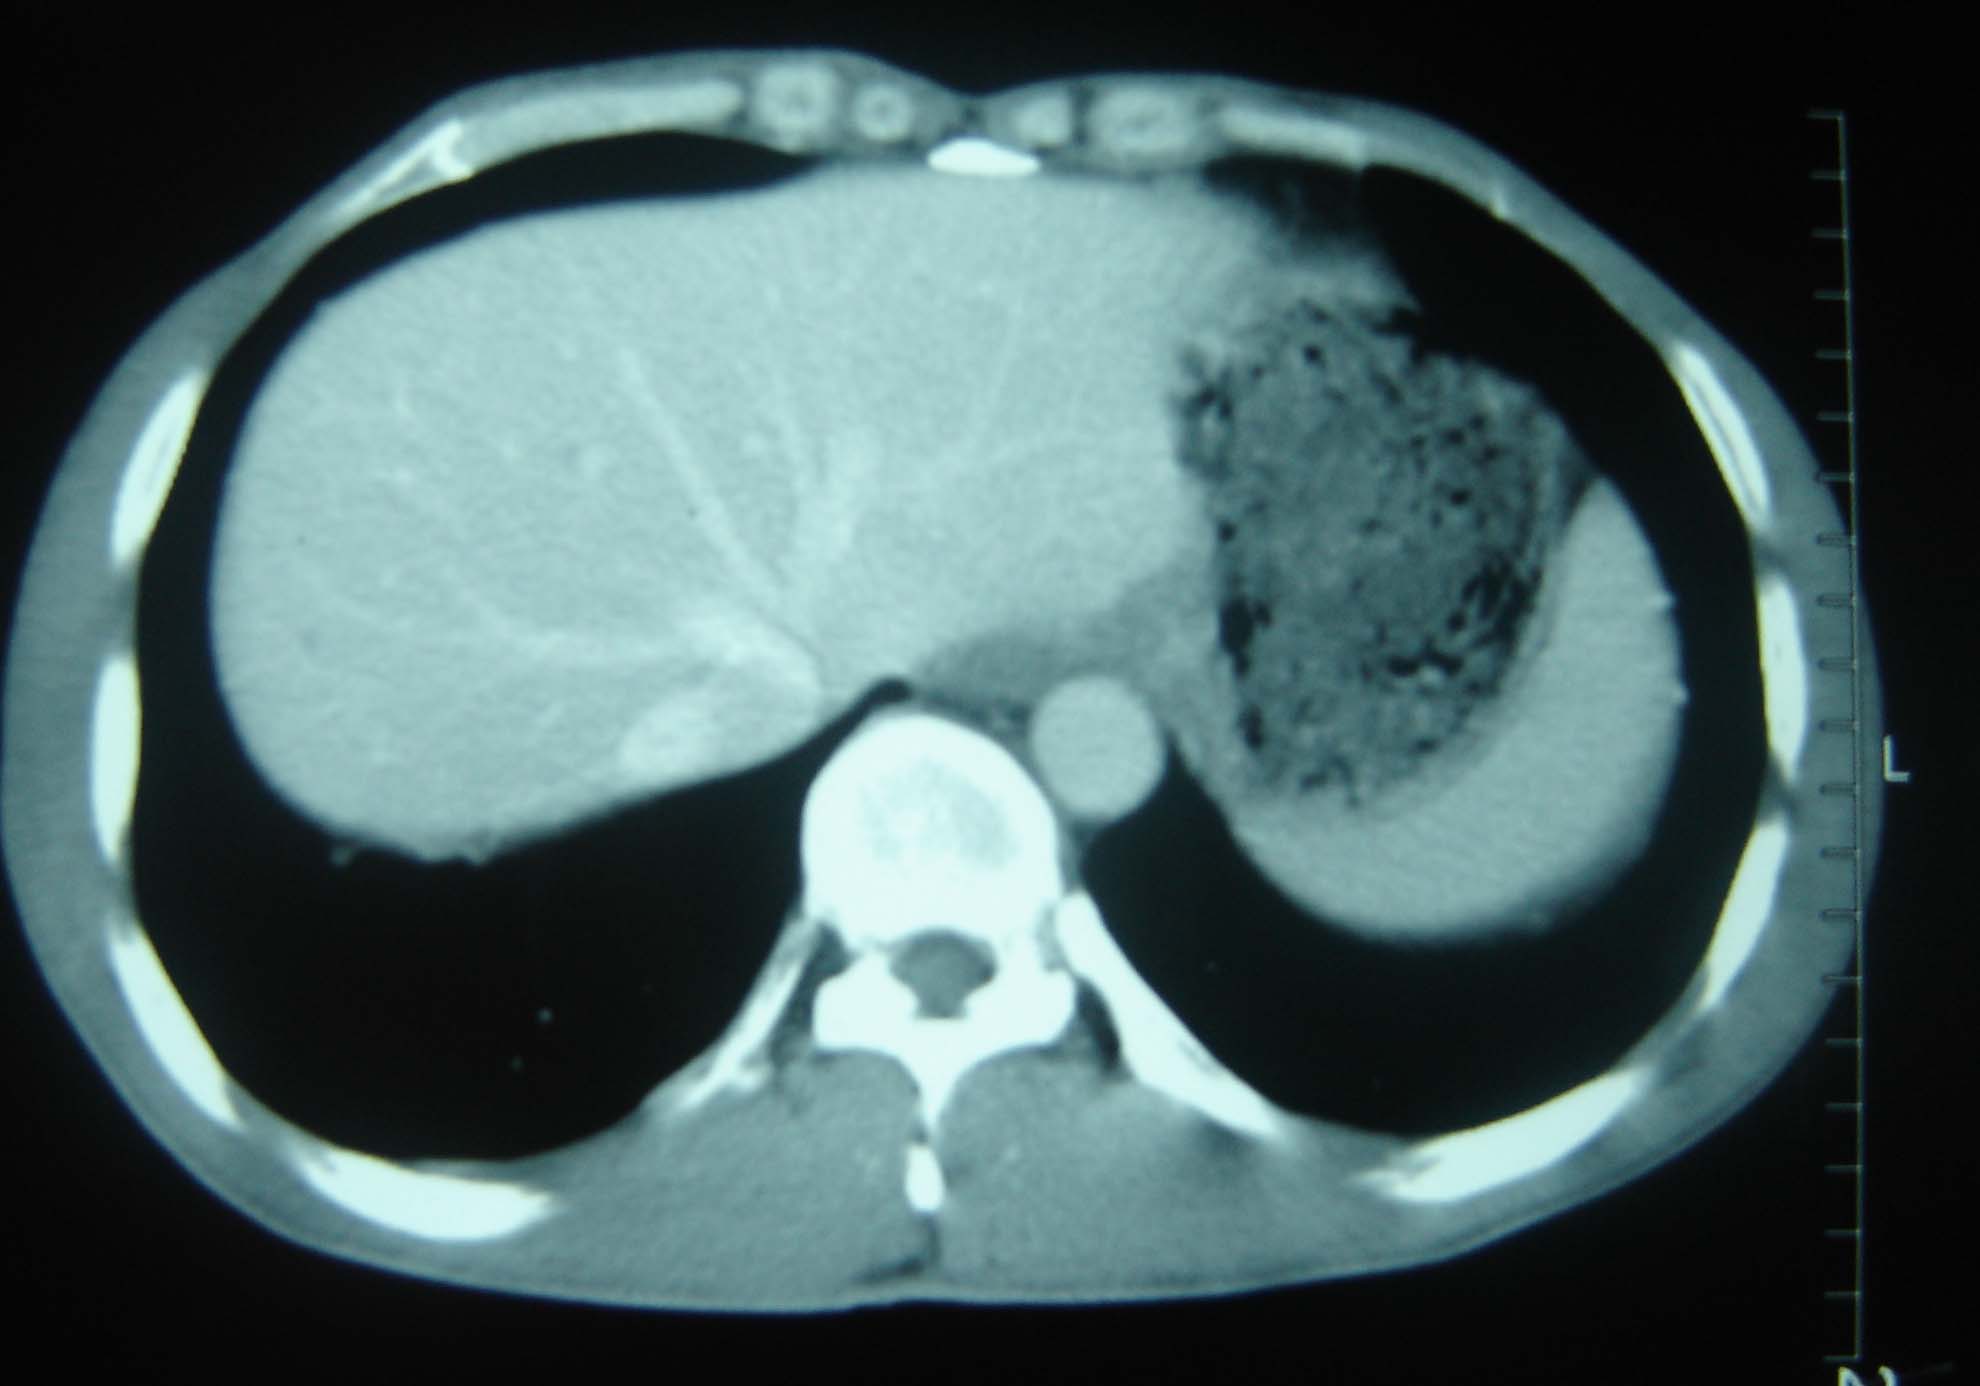

标题: CT25321:两肺多发结节 请会诊 [打印本页]

标题: CT25321:两肺多发结节 请会诊

男 、43岁,咳嗽胸痛,装修工,平时接触粉尘较多,有吸烟史10多年,纤维支气管镜检查未发现异常,胃镜、腹部b超检查亦未发现异常,颈部淋巴结活检未发现肿瘤细胞。

结节病?转移瘤?

1)考虑双肺及胸膜多发性转移瘤。2)肺气肿。

双肺结节病。